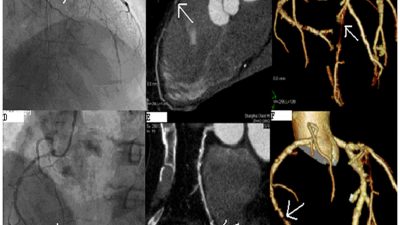

LimFlow Announces Positive Six-Month Data From Promise I U.S. Early Feasibility Study – Cath Lab Digest

Interesting new technology—early feasibility data for the LimFlow system for the teatment of chronic limb-threatening ischemia is positive, with the novel approach showing an encouraging amputation-free survival rate of 74 percent and 100 percent of wounds classified as healed or healing at nine months follow-up. “The minimally-invasive LimFlow system is designed to bypass blocked arteries in the leg and delivery oxygenated blood back into the foot via the veins,” reads the press release. Read more »